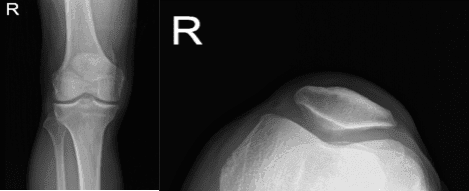

Un hombre de 50 años con molestias de dolor en la rodilla izquierda visitó nuestra consulta. Recuerda una lesión en una caída, que no puede presionar la rodilla. También dice que siente un espacio entre la rótula.

Fue examinado físicamente y se le realizó una resonancia magnética, que mostró una ruptura completa del cuádriceps junto con una rotura lateral del menisco y una rotura parcial del LCA. El paciente acudió a urgencias por un dolor intratable. Hablamos sobre las opciones de tratamiento y el paciente optó por el manejo quirúrgico.